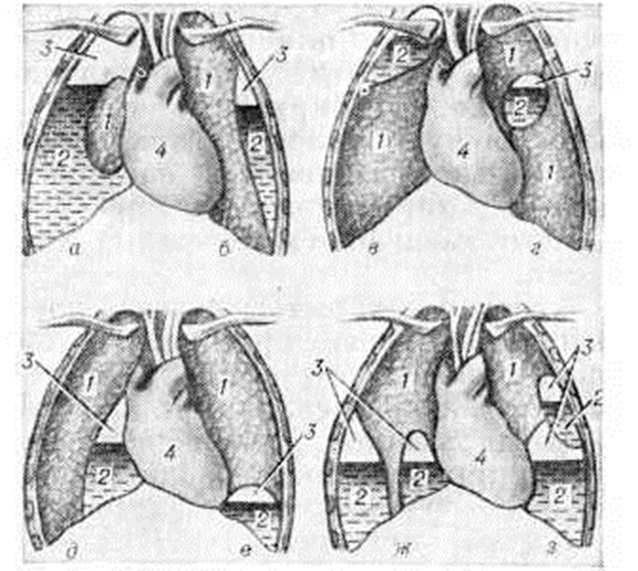

ПиопневмотораксПиопневмоторакс (греческий pyon гной + пневмоторакс) — одновременное скопление гноя, а также газа или атмосферного воздуха в плевральной полости. Классификация. По распространённости и локализации различают следующие виды Пиопневмоторакс: тотальный (напряжённый и ненапряженный) и ограниченный (осумкованный) — пристеночный, апикальный, междолевой, парамедиастинальный, наддиафрагмальный, многокамерный, в том числе сообщающийся и не сообщающийся (рисунок 1). По этиологии Пиопневмоторакс подразделяют соответственно виду возбудителя, вызвавшего нагноение в лёгком и плевральной полости. С. И. Спасокукоцкий выделяет следующие клинические, формы Пиопневмоторакс: острая, мягкая, стёртая. Возникновение этих форм зависит от локализации основного процесса в лёгком, характера микрофлоры, выраженности нагноительного процесса в лёгком, реакции плевры на воспалительный процесс. По времени развития Пиопневмоторакс при пневмонии различают парапневмонические и метапневмонические формы. Этиология. Причиной Пиопневмоторакс могут быть: пневмония (смотри полный свод знаний), абсцесс и гангрена лёгкого (смотри полный свод знаний Легкие), туберкулёз (смотри полный свод знаний Туберкулёз органов дыхания), проникающие ранения грудной клетки (смотри полный свод знаний Грудь), операции и диагностические манипуляции на органах грудной и брюшной полости, ущемление и перфорация полого органа брюшной полости при диафрагмальной грыже (смотри полный свод знаний Диафрагма) и другие Туберкулёзный Пиопневмоторакс возникает при прорыве субкортикально расположенных казеозных очагов либо в результате присоединения к туберкулёзному процессу банальной инфекции с последующей деструкцией лёгочной ткани и прорывом внутрилёгочной полости (полостей) в плевральную полость. Одной из причин Пиопневмоторакс является эмпиема плевры, вызванная Clostridium perfringens — микробом, ведущим к появлению газа в герметичной плевральной полости. Патогенез и патологическая анатомия. Независимо от этиологии прорывающихся в плевральную полость некротических очагов либо абсцессов изменения плевры в области прорыва однотипны и зависят от стадии процесса (угрожающий прорыв, открытый легочно-плевральный свищ, прикрытый легочно-плевральный свищ). Стадия угрожающего прорыва характеризуется наличием небольшого субплеврально расположенного гнойно-некротического очага, который разрушает соответствующую часть плевры. От плевральной полости этот очаг отделяет тонкая пластинка, образованная пограничной мембраной и поверхностным коллагеновым слоем плевры; сетчатые коллагеново-эластические слои при этом разрушены. После прорыва субплеврального некротического очага (стадия открытого легочно-плеврального свища) определяется небольшой участок неправильной формы, образованный рыхлым детритом. Снаружи некротическую зону ограничивает узкий слой воспалённой лёгочной ткани. В случае прорыва абсцесса диаметр свища достигает иногда 6 сантиметров и более, на плевре определяется большая язвенная поверхность, кратерообразно погруженная в ткань лёгкого. Количество проникшего в плевральную полость газа зависит не только от величины свища и абсцесса. Решающими факторами при этом являются интенсивность поступления газа в плевральную полость, зависящая от калибра сообщающегося бронха и его проходимости, а также скорость резорбции газа из плевральной полости. При наличии в бронхе, дренирующем гнойную плевральную полость, клапанного механизма развивается напряжённый Пиопневмоторакс, характеризующийся повышенным давлением в плевральной полости. В стадии прикрытого легочно-плеврального свища противоположные края свища вместе с соседними участками плевры склеиваются и дефект закрывается. Дальнейшая судьба прикрытых свищей различна: они рубцуются или вновь открываются в плевральную полость. При проникающих ранениях грудной клетки Пиопневмоторакс возникает вследствие инфицирования крови, излившейся в плевральную полость. Наиболее часто в этих случаях Пиопневмоторакс развивается при попадании в плевральную полость инородных тел (осколков, обрывков одежды). Клиническая картина зависит от скорости возникновения Пиопневмоторакс и выраженности гнойно-резорбтивной лихорадки. |